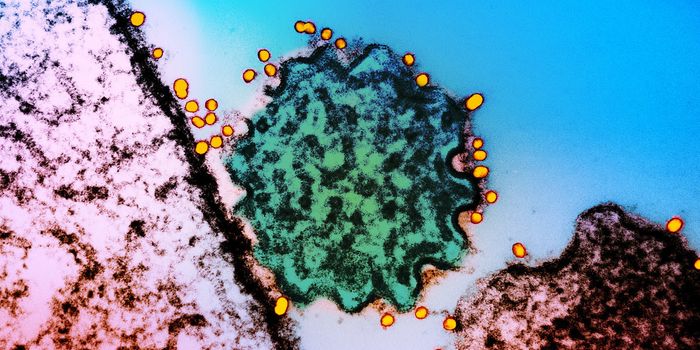

AUG 24, 2020ImmunologyOnce in the body, HIV tracks down T cells that bear the CD4 receptor. It attaches to these immune cells, fusing itself w ...